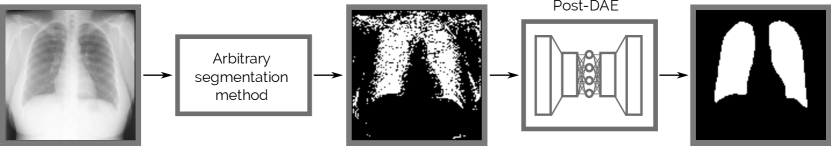

Refer to caption

Figure 1: Post-DAE works as a post-processing step and improves the anatomical plausability of segmentation masks obtained with arbitrary methods.

In this work, we introduce Post-DAE (post-processing with denoising autoencoders), a post-processing method which produces anatomically plausible segmentations by improving pixel-level predictions coming from arbitrary classifiers (e.g. CNNs or RF), incorporating shape and topological priors. We employ Denoising Autoencoders (DAE) to learn compact and non-linear representations of anatomical structures, using only segmentation masks. This model is then applied as a post-processing method for image segmentation, bringing arbitrary and potentially erroneous segmentation masks into an anatomically plausible space (see Figure 1).